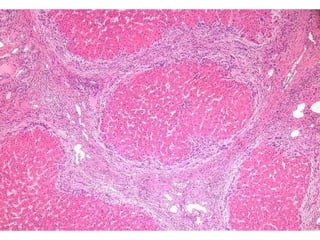

LS08-10290 Abnormal LFT, negative for Hepatitis A, B, C.  Sono: heterogeneous liver.

BS09-10453:  Dx: Chronic hepatitis, with severe activity (focal parenchymal collapse) and cirrhosis, suggestive of autoimmune hepatitis. Corresponds to: Modified Ishak stage 4/4 Metavir F4